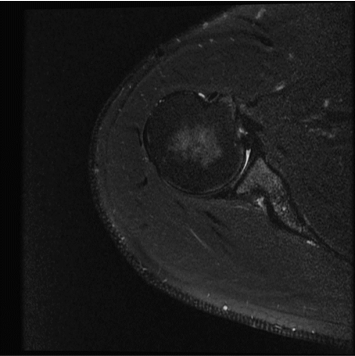

384 x 256 (4 NEX)

2:59 minIAI (Innovative AI)

384 x 256 (2 NEX)

1:28 minReduced Scan Time

384 x 256 (2 NEX)

1:28 minConventional

384 x 256 (4 NEX)